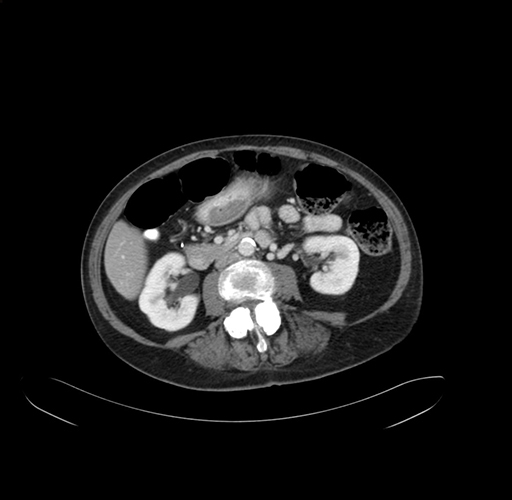

Pre-Chemo: Coronal Venous

Coronal Venous